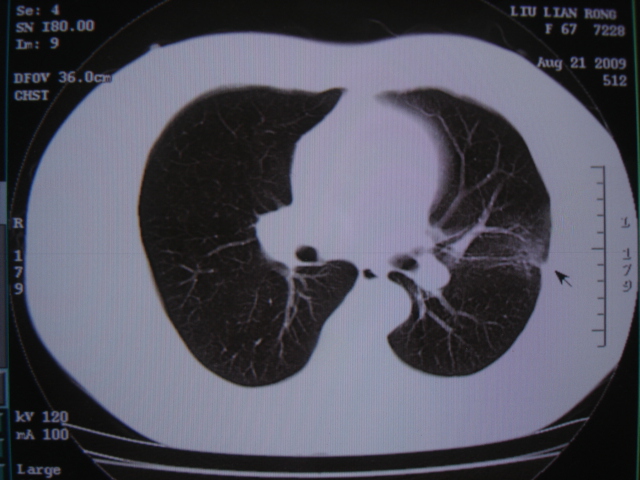

第三次ct2009.8.21

病灶与胸膜成直边征,考虑炎症假瘤可能性大。

考虑左肺上叶炎症感染(炎性假瘤可能)。

考虑左肺上叶炎症感染,以炎性假瘤可能性大。